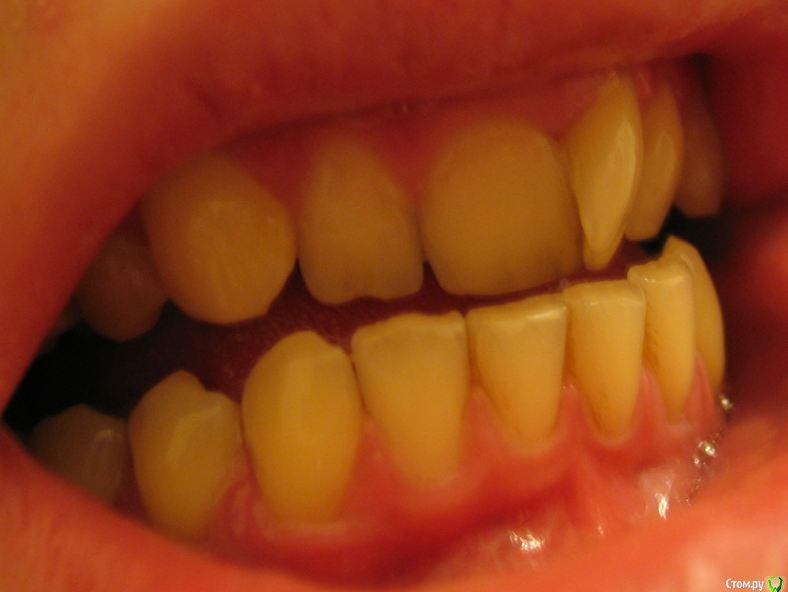

Мне 28 лет. У меня нет ни одной пломбы. Всю жизнь я хожу к стоматологом только на гигиеническую чистку. Последние несколько лет мне уже несколько врачей рекомендовали удалить четвёрки и поставить брекеты для исправления дистального прикуса. Один из ортодонтов также предлагал ЧЛХ нижней челюсти. Основной аргумент у врачей, что если не снизить нагрузку на дёсны от неправильного прикуса, то уже лет через 5 зубы начнут выпадать. Как видно на фото, дёсны уже значительно сползли, появился клиновидный дефект. С эстетической точки зрения меня всё устраивает. Хочу услышать ещё несколько мнений, как бороться с опусканием дёсен и стоит-ли заниматься исправлением прикуса.